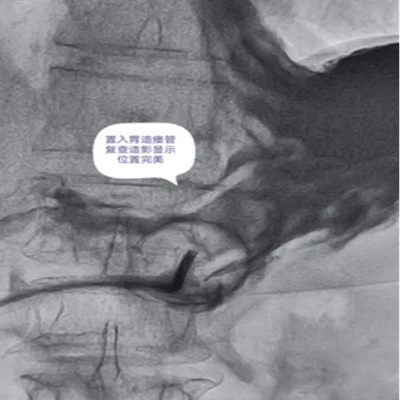

DSA引导下经皮胃造瘘术,是在数字减影血管造影(DSA)这个“透视眼”的实时可视化导航下,于患者腹壁上建立一个仅 3-5毫米 的微小穿刺点。通过这个“针眼”,医生精准地将一根营养管直接置入胃部,建立起一条直达的营养通道。

整个过程就像一次精准的“导航穿刺”,全程操作便捷、创伤小,却能完美替代传统的鼻饲管,为患者提供长期、稳定、安全的营养支持。

医院临床实践中就有典型案例:一名65岁食道癌伴淋巴结转移患者,因食道狭窄无法插入胃镜,且体质虚弱难以耐受全麻手术,团队借助DSA精准导航,仅用10分钟便完成手术,局部麻醉下患者全程无明显不适,术后1天即可通过造瘘管补充营养,为后续抗肿瘤治疗顺利开展奠定了坚实基础。